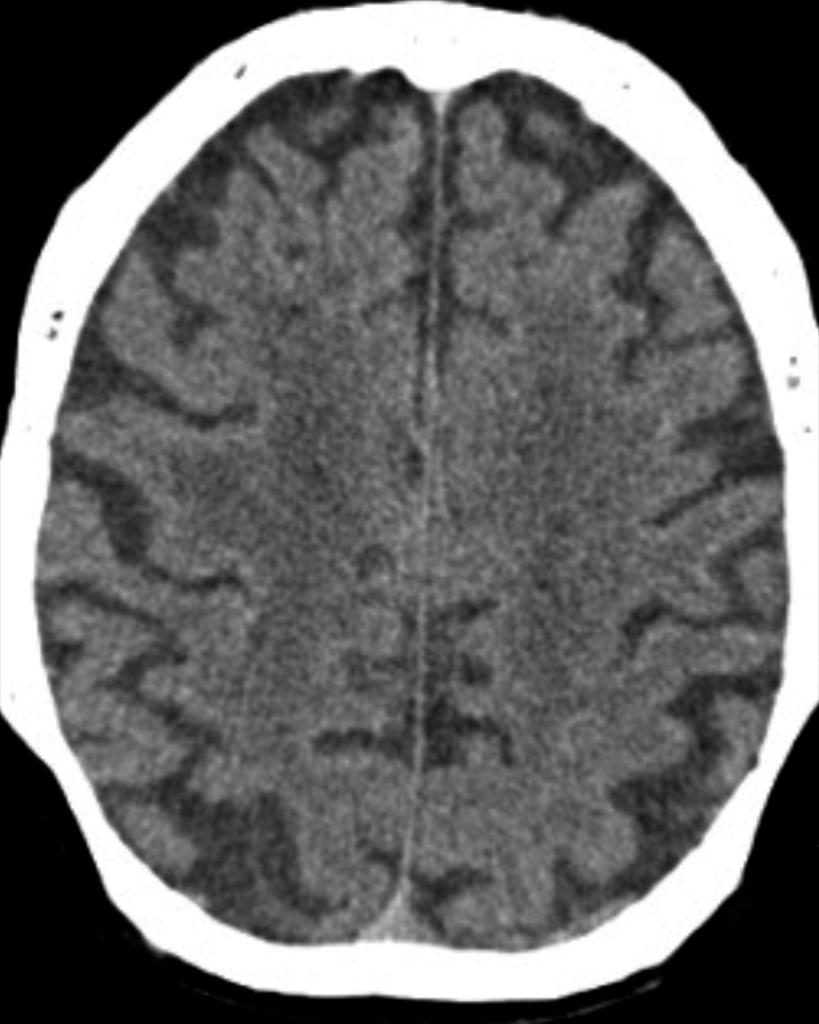

Pathology